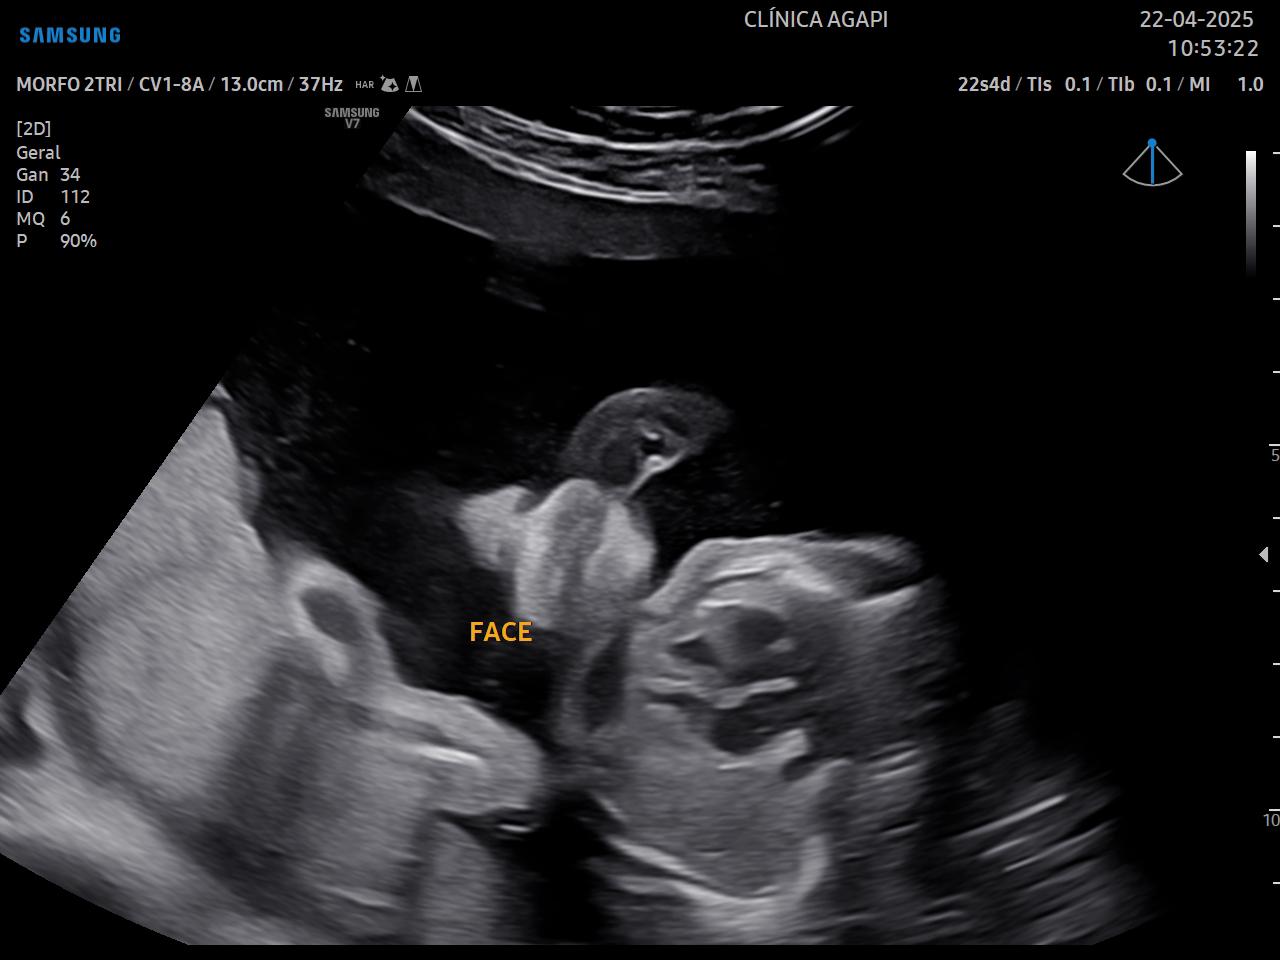

Realizado preferencialmente entre 20 e 24 semanas de gestação, seu objetivo principal é avaliar a anatomia fetal de forma detalhada e detectar possíveis malformações.